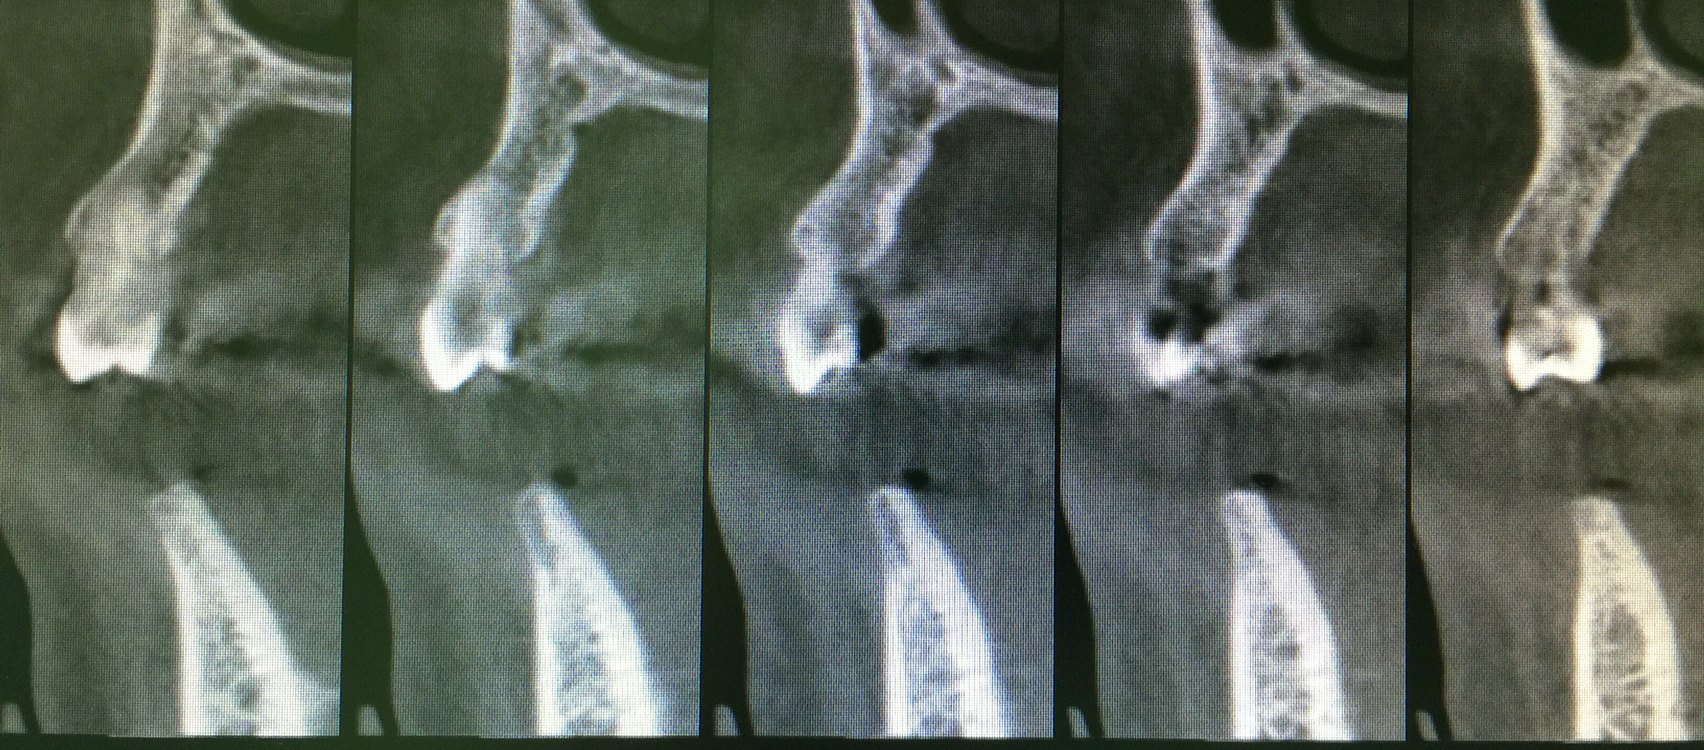

這就需要CT檢查,下圖是口腔CBCT的結(jié)果,我們看到缺牙區(qū)的牙槽骨寬度極窄處只有不到3毫米,顯然不是理想的種植牙條件。如果臨床檢查寬度理想,全景片檢查高度理想的情況下,就可以不用拍口腔CBCT。

口腔CBCT